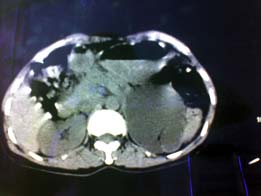

标题: CT20999:邓主任 用手机拍的

患者女  外伤    b超示左肾脏积水    左输尿管扩张    现在法医就是要看有没有肾脏损伤

1、肾实质未见异常密度影。

2、结合b超,考虑左输尿管下段梗阻,原因待查。